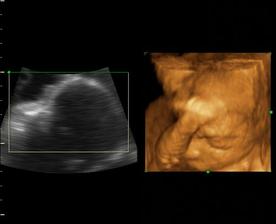

Naša maličká Emka alebo Silvinka...🙂

Od 19. júna 2008, teda od 21. týždňa vieme, že sa nám na 99% narodí dievčatko...na mene neodznela ešte úplná zhoda, preto Ema alebo Silvia...no ja dúfam, že sa mi podarí presadiť Emu, aj keď Silvia je tiež krásne meno...🙂...